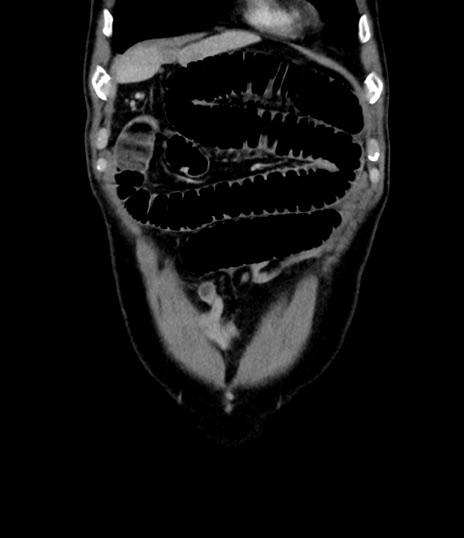

横断像